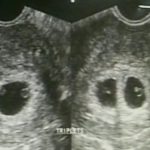

Look: Mayor Sara Duterte’s Utrasound Reveal Triplets

Mayor Sara Duterte

Mayor Sara Duterte is currently pregnant and expects a triplets in the coming months. Mayor Sara Duterte has recently been reported apologizing to the people of Davao for not being in the crowd lately as she is pregnant with a multifetal pregnancy. Confirmed in the previous report, the presidential daughter and her family is expecting … Read more